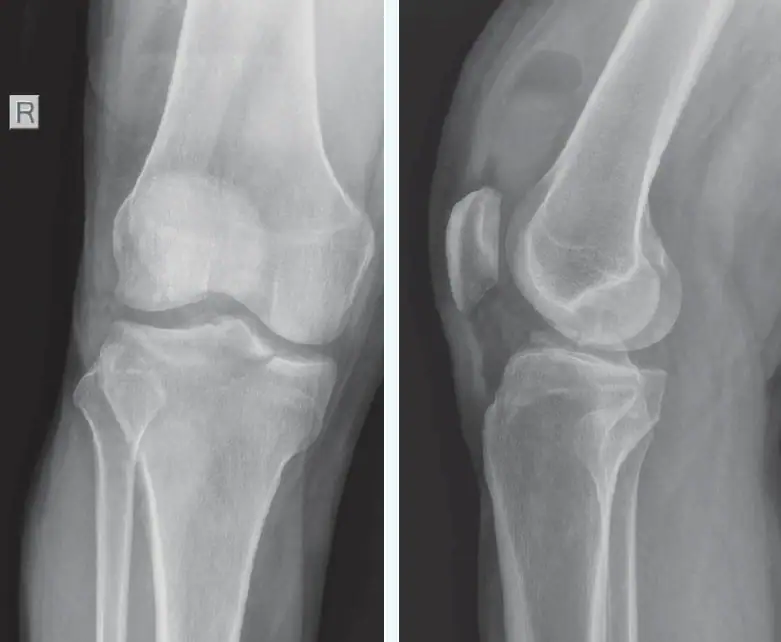

A 38-year-old otherwise healthy male presents to urgent care with acute right knee pain following a 6-foot fall from a ladder, landing directly on his right lower extremity 2 hours prior to arrival. He reports severe pain and the inability to bear weight since the injury. Physical examination reveals that he is afebrile with normal vital signs. Musculoskeletal exam is notable for moderate knee effusion with surrounding early ecchymosis, and medial joint line tenderness. There is pain with passive range of motion. Neurovascular assessment is unremarkable with normal sensation, brisk capillary refill, and no edema seen distal to the knee.

Review the images and consider what your diagnosis and next steps would be. Resolution of the case is described on the following page.